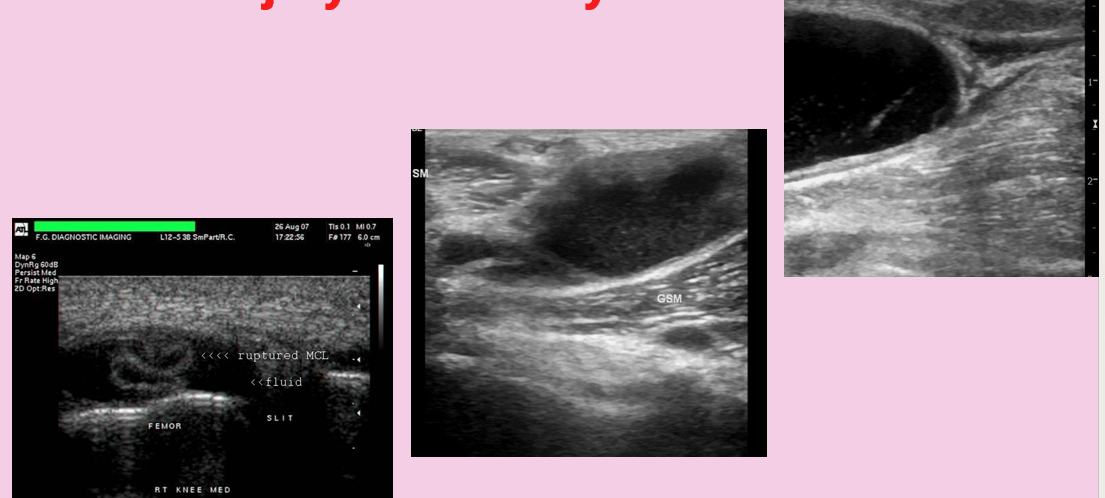

what is this?

muscle injury/bakers cyst

soft tissue masses

benign

lipoma (most common)

firboma

leiomyoma

pseudoaneurysm